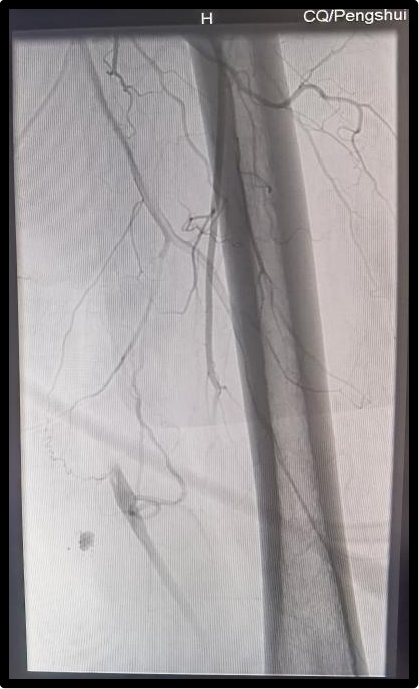

患者手术前,手术后的血管造影对比图如下:

患者凌女士,47岁,因“左下肢酸痛、麻木1+月”在外检查提示左侧股浅动脉闭塞可能。2021年07月09日为求进一步诊治来到河豚直播体育app。经支医专家张峰副主任医师(山东聊城市人民医院血管外科)及医院肝胆血管外科主任(副主任医师)王启伦详细询问病史、查体及完善相关辅助检查后,制定了双侧髂股动脉造影术、左股浅动脉球囊逐级扩张+支架植入术的方案。通过对凌女士的身体状况及手术风险的充分评估,在取得患者及家属的知情同意选择权后,肝胆血管外科医疗团队在介入手术中心的通力合作下,成功完成了我县首例髂股动脉造影、股动脉球囊扩张+支架植入术。整个手术过程顺利,患者术后在医护人员精心的治疗和护理下无术后并发症发生,目前已康复出院。7月22回访凌女士未感不适,恢复良好。